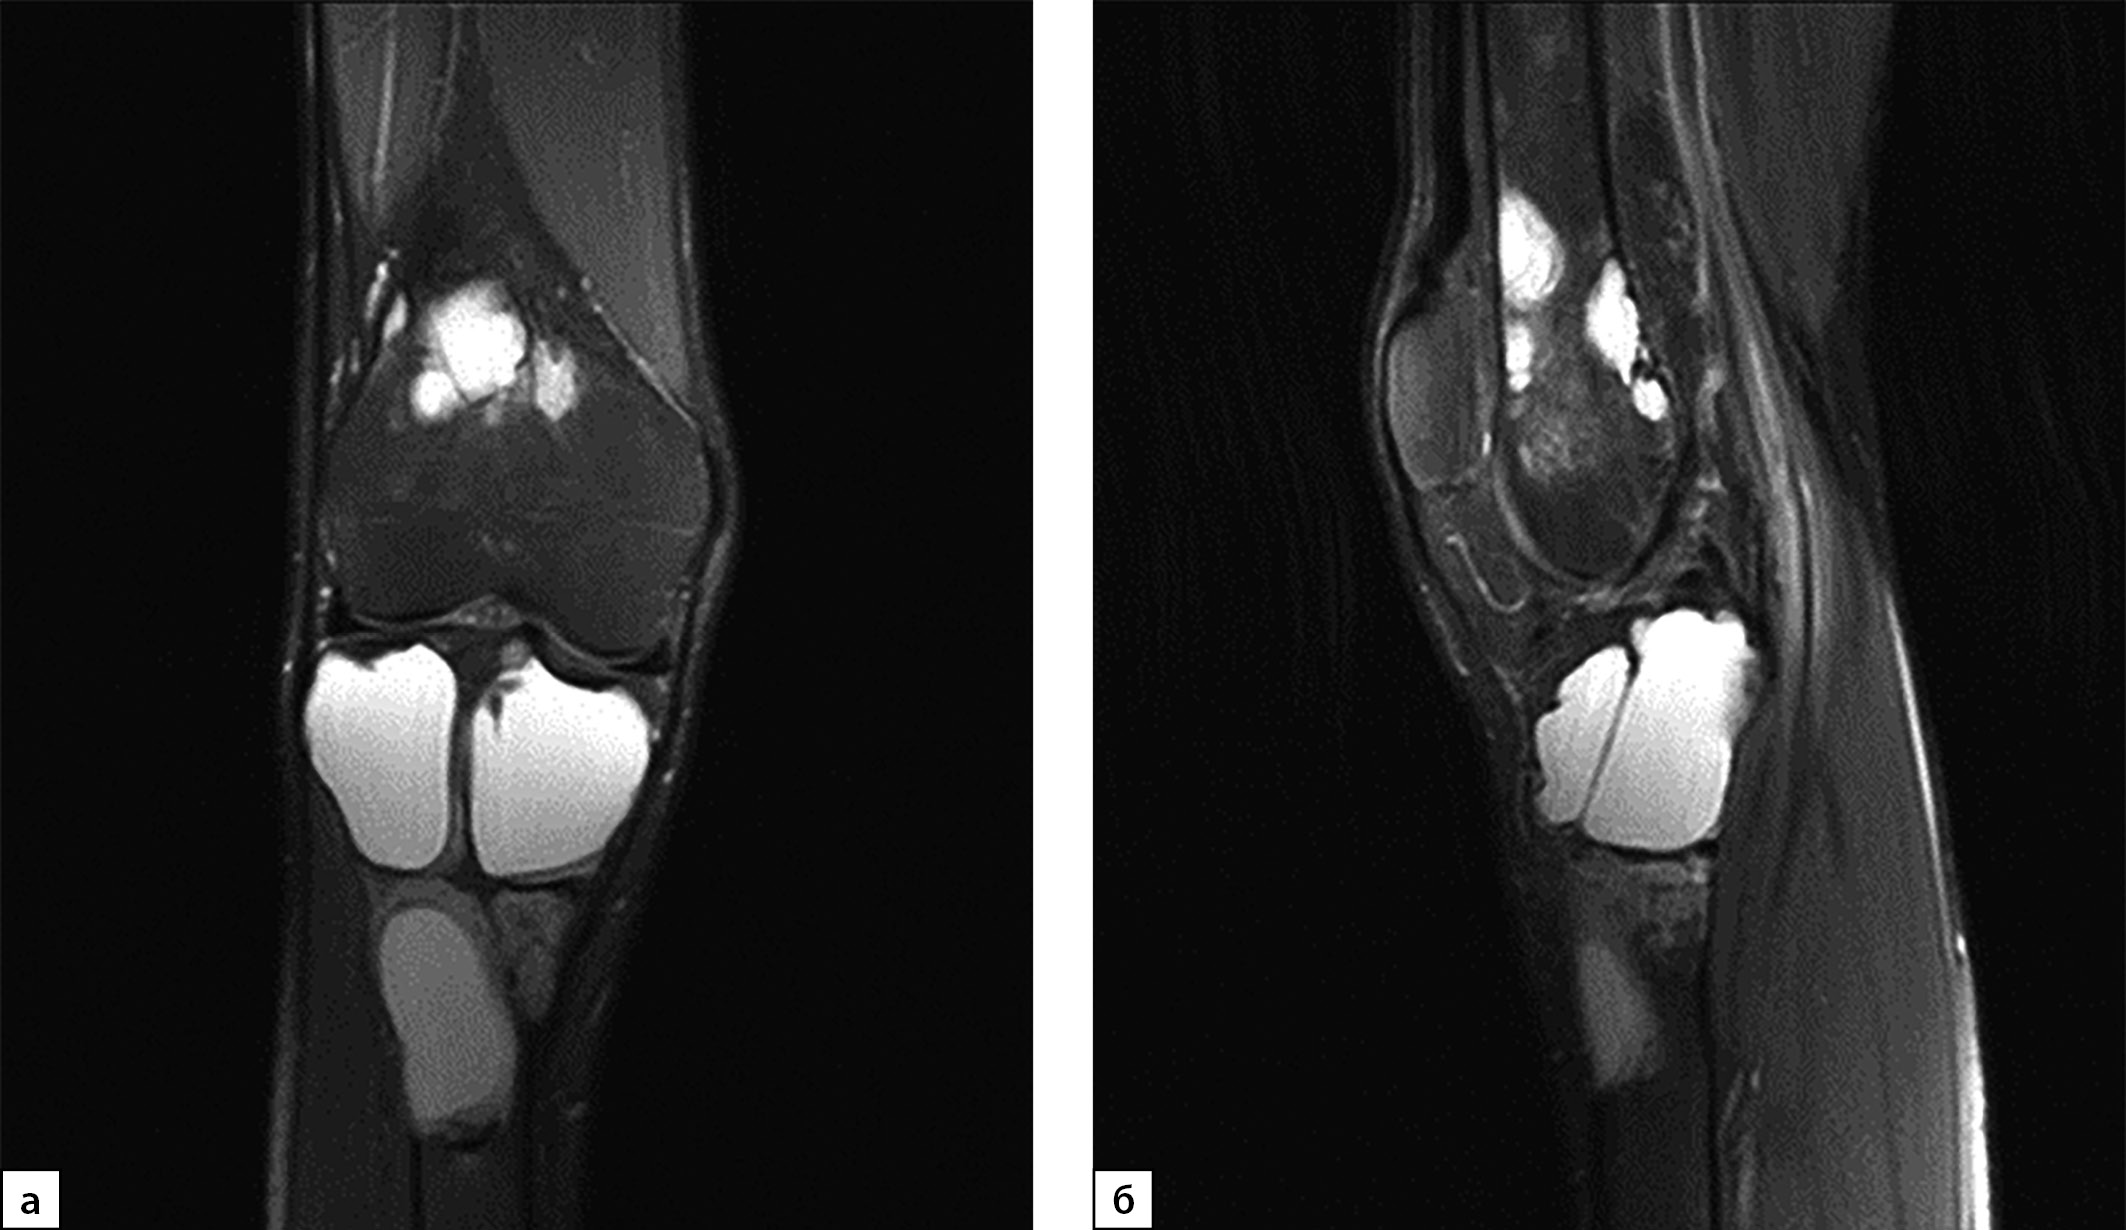

В июле 2020 г. после низкоэнергетической травмы (падения) при рентгенологическом исследовании правого коленного сустава выявлены множественные очаги деструкции костей, образующих коленный сустав. Данные изменения расценены как множественные кисты (рис. 1, а, б). По данным магнитно-резонансной томографии (МРТ) также подтверждены признаки множественных кист в дистальных метаэпифизах бедренных и проксимальных отделах большеберцовых костей с обеих сторон, справа — с разрушением кортикального слоя кости (рис. 2, а, б).

Рисунок 2. Магнитно-резонансная томография правого коленного сустава в режиме Т2, 2020 г. (в корональной (а) и сагиттальной проекциях (б)): МР-картина множественных костных кист в бедренной и большеберцовой костях. Отмечается истончение кортикального слоя кости, местами вздутие.